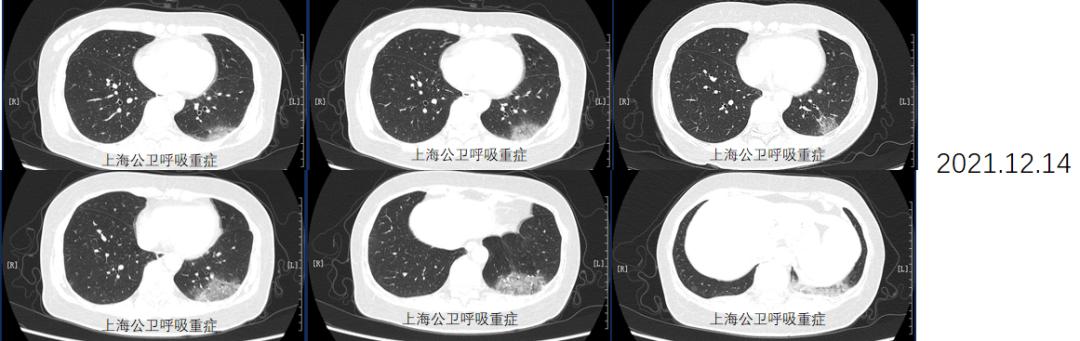

2021-12-14

胸部CT:1、右肺下叶外基底段及左肺下叶后基底段胸膜下感染性病变,请结合临床治疗后复查。2、两肺多发实性及磨玻璃结节,良性,请年度随访。较外院CT无改善。

同时给予激素治疗,加用甲强龙40mg,后序贯口服强的松40mg口服,逐渐减量,于2022.1.20及2022.7.14分别复查胸部CT,病灶明显吸收好转。